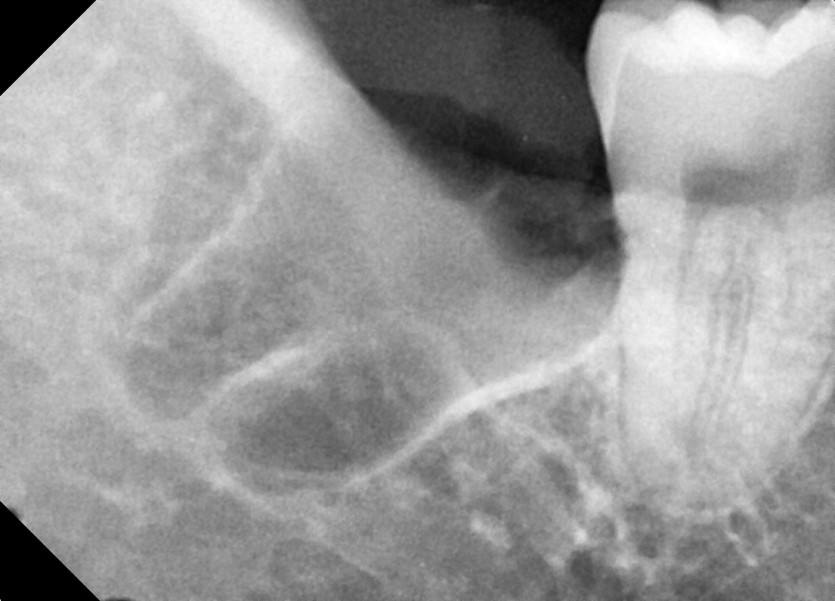

#18,48 사랑니 발치

구강외과 전문의가 당일 발치했습니다.